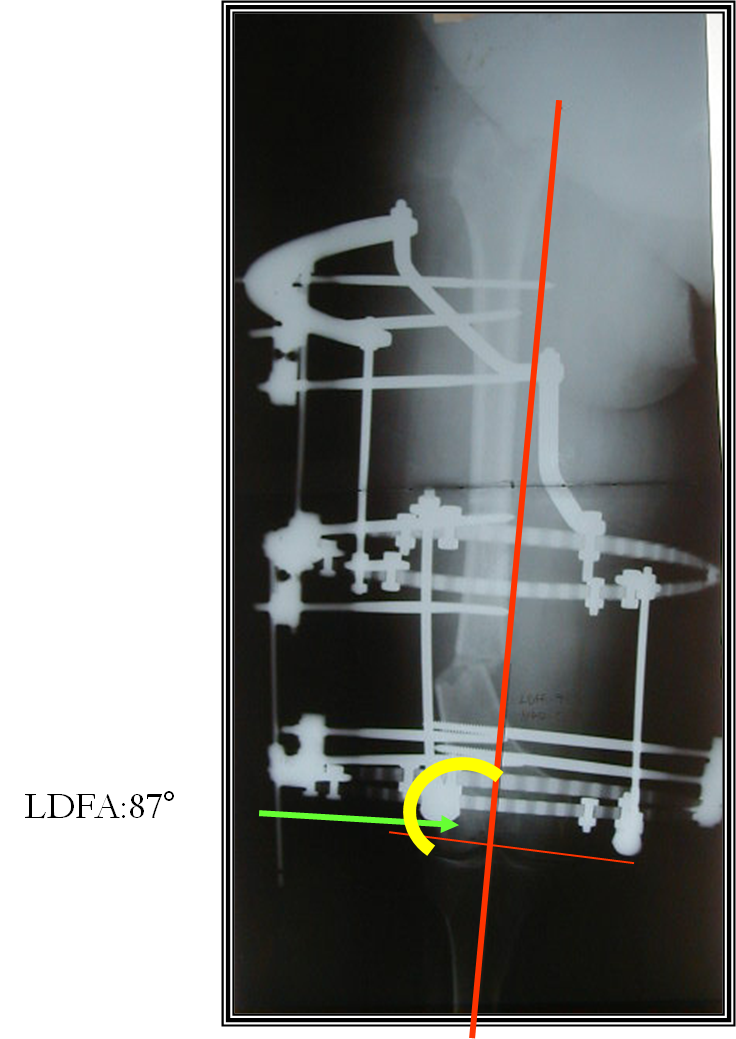

arthritis deformity surgery endoprosthesis hip prosthesis ilizarov ilizarov surgery infected nonunion knee prosthesis lengthening surgery limb lengthening surgery nonunion periprosthetic infection psodoartroz revision surgery total hip prosthesis total knee prosthesis